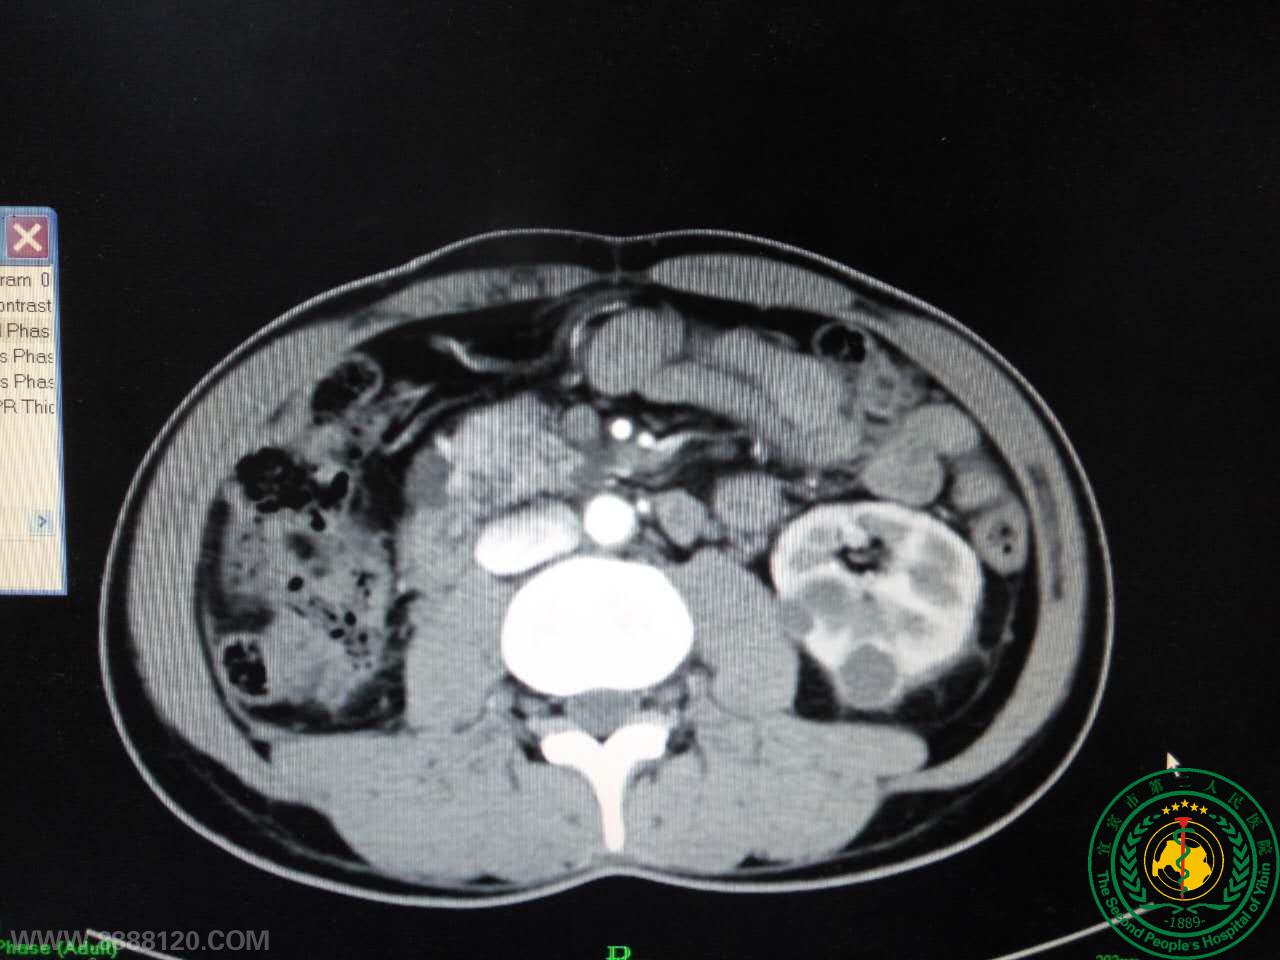

我科完成一例肾多发复杂肿瘤切除术

我科完成一例肾多发复杂肿瘤切除术13767